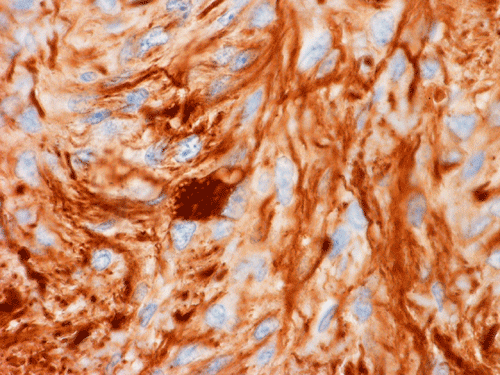

GFAP

Pathology of the Case: MRI shows a large mass with the more solid component located in the lateral ventricles and the cystic component protruding into the cortical area. The solid area is enhanced (Panel A). On low magnification, the lesion has alternating area of high and low cellularity (Panel B) with scattered calcifications in some of the sections. Medium and high magnification demonstrates perivascular coronary arrangement of cytoplasmic processes (Panel C, D, and E). The nuclei are bland and mitotic figures are not readily seen. Randomly scattered brown pigment containing cells are found in multiple areas of the tumor (Panel F, G, and H). Scant lipidized cells with enlarged nuclei (Panel I) are also present. The tumor cells are strongly positive for glial fibrillary acidic protein (GFAP) (Panel J and K) and S100 protein but are negative for epithelial membrane antigen (EMA), neurofilament proteins, and NeuN. The overall Ki67 labeling is low but focal small areas (about the size of one high power field) has increased labeling. The pigment appears to be melanin on microscopic examination. These pigments are positive with Fontana-Masson stain (Panel L) but negative for Prussian blue stain for iron (Panel M). These features confirmed that these are melanin pigments. The pigment granules are positive for periodic acid-Schiff reaction (N), negative for Ziehl-Neelsen (acid fast) stain..

Immunohistochemistry

Ependymomas often display significant amount of immunopositivity for glial fibrillary acidic protein (GFAP). They are often but not always positive for epithelial antigen (EMA). The lumninal surface of ependymal rosettes can be strongly positive for epithelial membrane antigen. The same is true for the surface of papillary ependymal ependymoma. EMA positive reaction can also occur as positive dots in tumor cells. The staining can have a cluster pattern of distribution. However, most tumors are only focally positive.